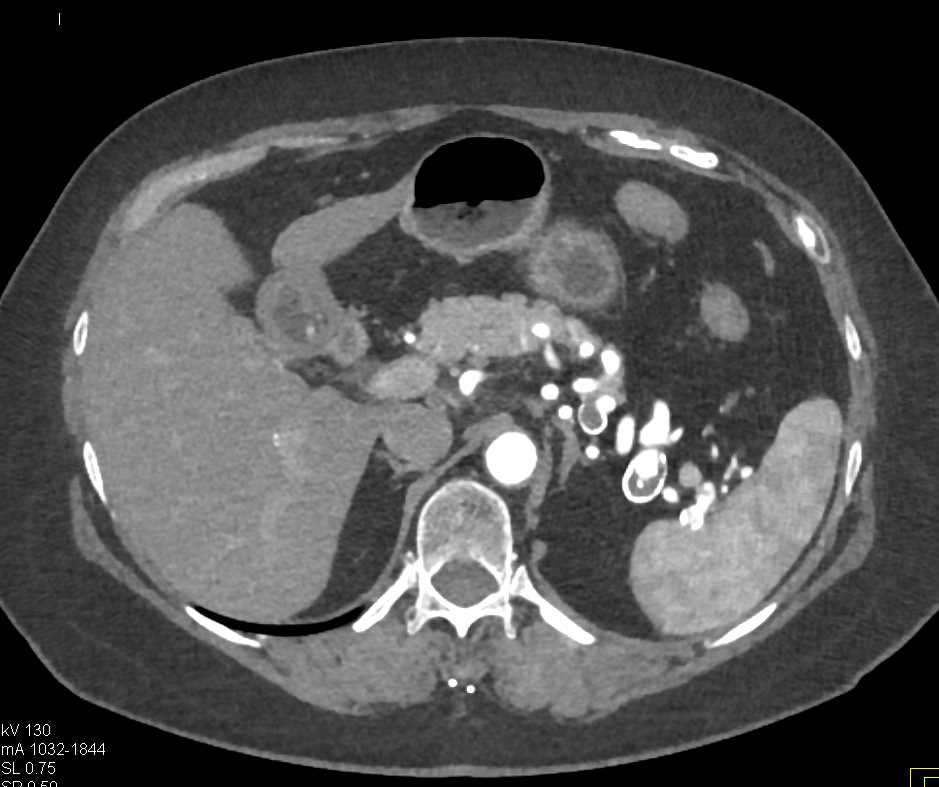

Carcinoid Tumor Root of Mesentery with Desmoplastic Reaction